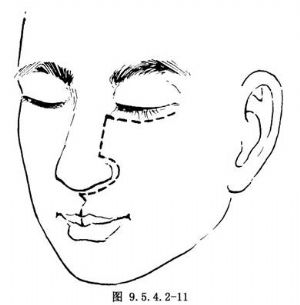

(2)自骨膜下分離頰部軟組織瓣並翻向外側,切斷眶下神經,顯露眶下緣,上頜竇前壁,梨狀孔,上牙槽骨上部及顴骨(圖9.5.4.2-12)。